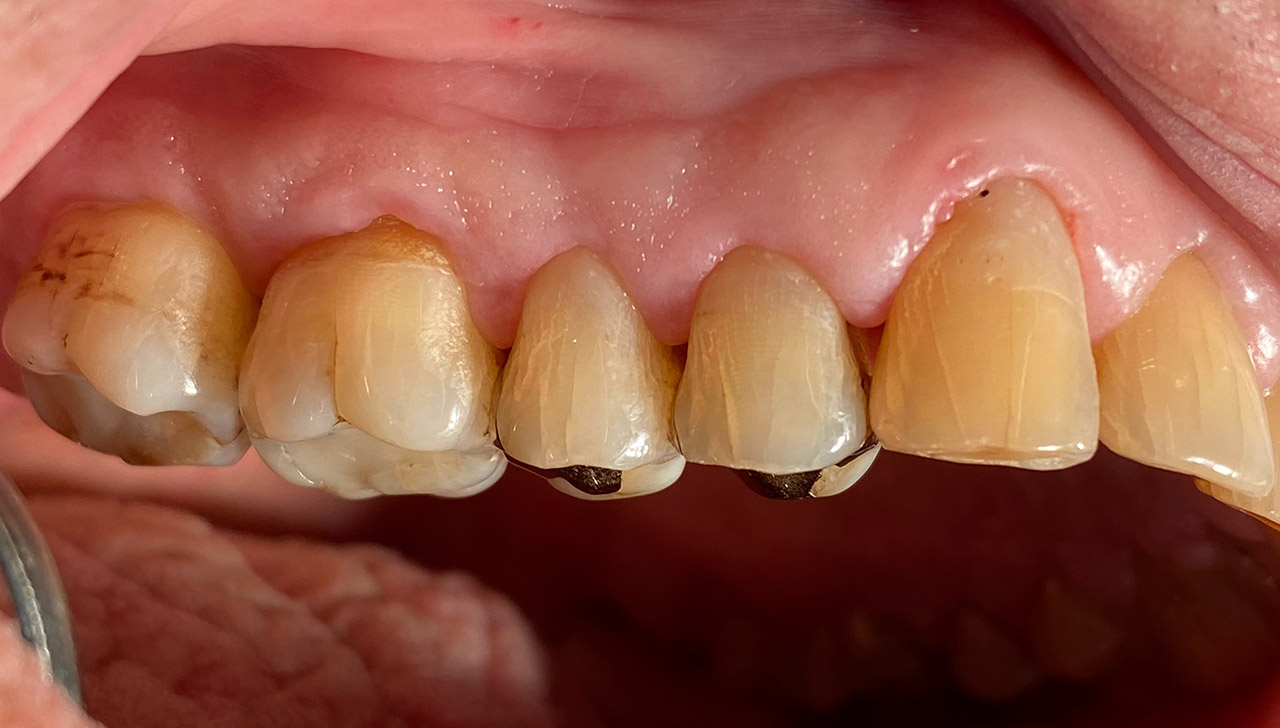

Nach Unfall mit E-Scooter unbefriedigendes Ergebnis der Erstversorgung (alio loco). Therapievorschlag: Stiftzähne?

Unsere minimalinvasive Therapie: Revision der Wurzelbehandlungen, danach internes und externes Bleaching, adhäsive Kunststoffüllungen in Schichttechnik. (Titel meiner Diplomarbeit 2003 “Die Vermeidung von Extraktion und Wurzelspitzenresektion durch zeitgemässe Endodontie in der Privatpraxis”)